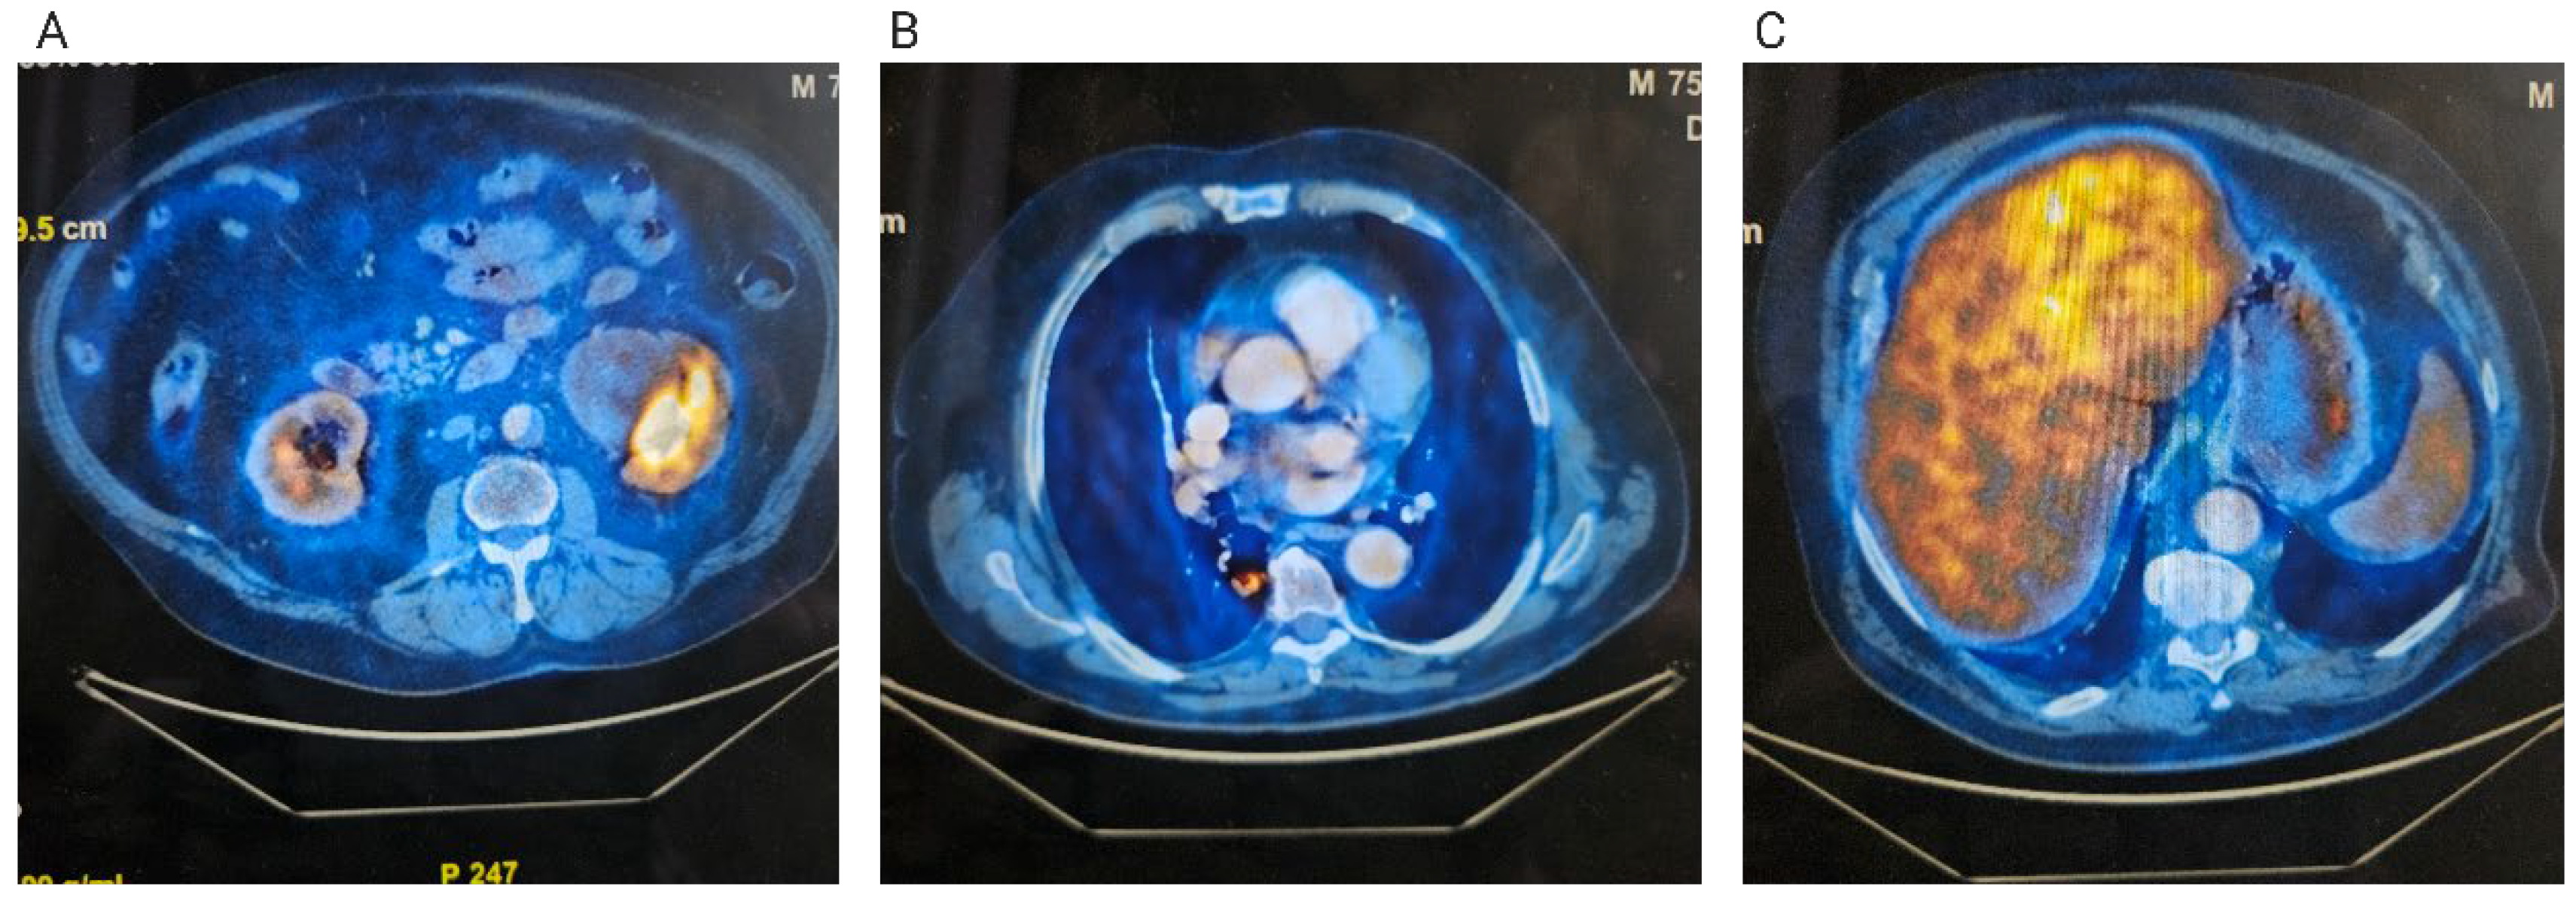

2. Case Presentation